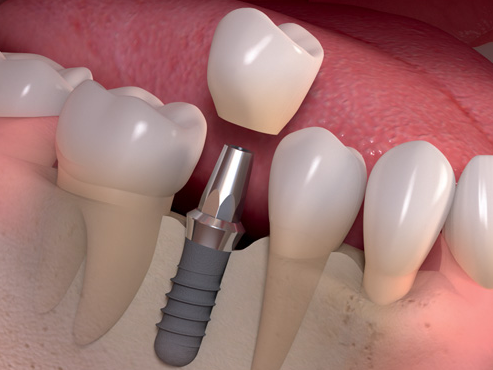

Mất răng là một trong những vấn đề ảnh hưởng nghiêm trọng đến tình trạng sức khỏe răng miệng, và làm giảm đi nét đẹp trên khuôn mặt. Khi một hoặc nhiều răng bị mất đi dẫn đến những răng còn lại có khuynh hướng mọc lệch lạc.